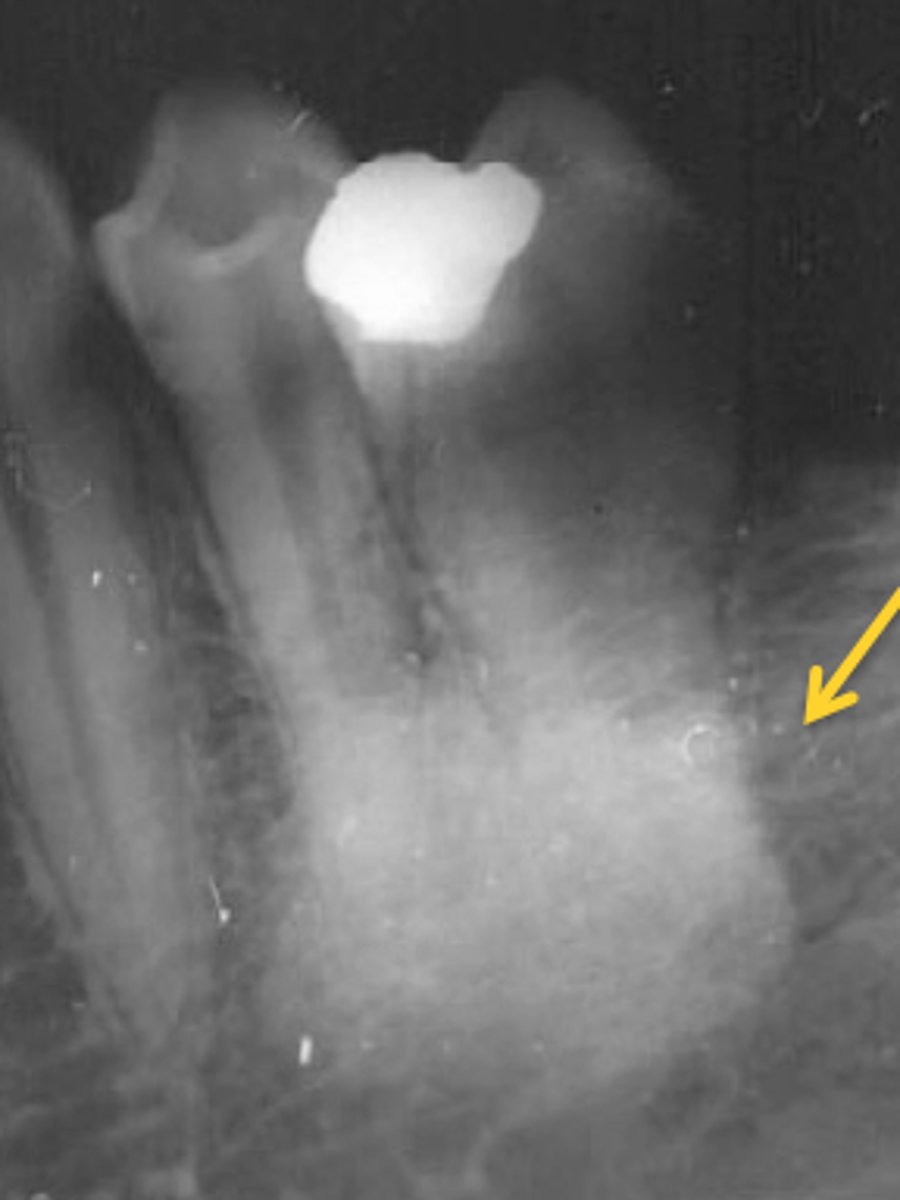

periapical

radiographic image showing the crown, root tip, & surrounding structures

periapical radiographs used to detect:

any abnormalities of the root structure & surrounding bone structure

Dilaceration in a radiographic image indicates the:

root shape is abnormally bent or curved